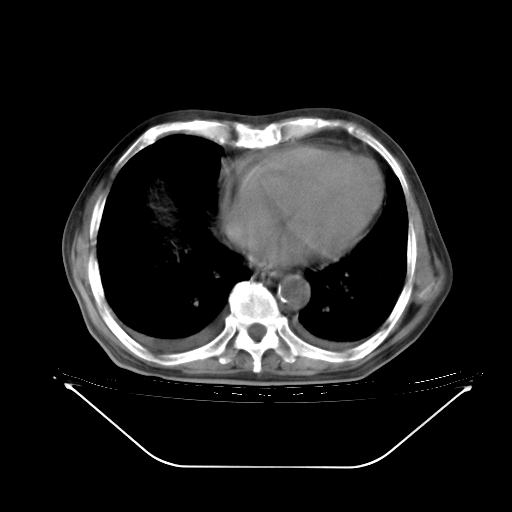

今天复查肺部CT,发现双肺广泛磨玻璃样改变。所以我把3月19日和5月9日相隔50天的肺部CT上传。请大家会诊。

5月9日肺部CT(在4月27日齐鲁医院肺部CT描述部分肺组织磨玻璃样改变,12天后肺组织广泛磨玻璃样改变)

2009年5月9日肺部CT